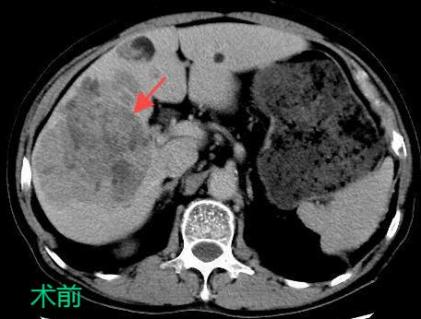

TACE/HAIC:經(jīng)肝動(dòng)脈灌注化療栓塞(TACE)、肝動(dòng)脈內(nèi)灌注化療藥物(HAIC)是在不開(kāi)刀暴露腫瘤病灶的情況下,在皮膚上做直徑幾毫米的切口,在影像設(shè)備的引導(dǎo)下,導(dǎo)絲和導(dǎo)管插入肝臟腫瘤血管,注入栓塞劑和化療藥物使肝臟腫瘤內(nèi)化療藥物濃度提高,并減少全身的藥物總濃度,達(dá)到提高化療效果并減少毒副作用的目的。對(duì)于無(wú)法手術(shù)切除的巨塊型肝癌、肝內(nèi)多發(fā)肝癌病灶、肝癌結(jié)節(jié)破裂出血有良好的治療效果。

bd76aa52bb6546a69be60729c8730795.Jpeg

7c270a27028043a8ba4cb33fa1c0ed79.Jpeg

097218efe36240c99faa29fefe0fd54e.Jpeg

癌的介入治療